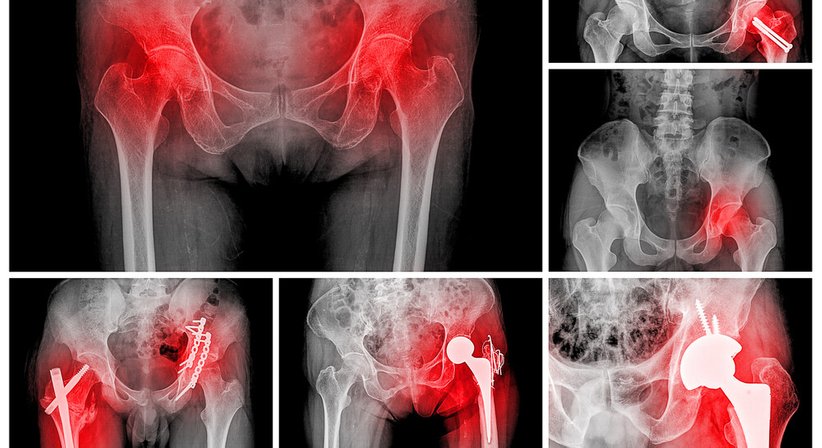

Liegt ein schwerer Gelenkverschleiß an Hüfte (Coxarthrose) und Knie (Gonarthrose) vor, der die Beweglichkeit und Lebensqualität des Betroffenen stark einschränkt, bleibt nach Ausschöpfung aller konservativer Therapien oftmals nur noch der Einsatz eines künstlichen Hüft- oder Kniegelenks.

Die Implantation der Hüft- und Knieendoprothese erfolgt mit minimal invasiver Technik, um eine möglichst rasche Rehabilitation zu erreichen.